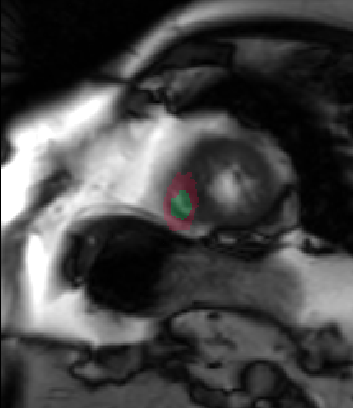

Table 2 summarizes the results of our method for RV segmentation in terms of image-based metrics. The results show that the algorithm performs better at ED than ES. This can be explained by the fact that the image quality is higher at ED than at ES. By analyzing the DM and HD on a slice-basis, it can be seen that the proposed method has a high performance on basal slices, with an average and . However, the segmentations on apical slices are of lower quality affecting the overall DM and HD scores. Figure 3 shows segmentation results in six different cases obtained from the challenge that illustrate the differences between basal and apical segmentations.

The results show that the method perform well on average but there are some cases in which it fails. In particular, our method has a very high performance on the basal slices, whereas the scores obtained for apical slices are lower (Figure 3). These can be explained by two factors: 1) The image quality at the apical slices is rather low. As the registration, the atlas ranking and the label fusion are intensity-based, poor image quality can affect the results, and 2) the regions to be segmented at the apical slices are rather small, which implies that the atlases’ masks are also small at these slices. When the masks are used in the registration process to supress undesired structures, the remaining information is insufficient, causing the intensity-based registration, rigid or non-rigid, to fail.

In conclusion, we have presented a fully automatic segmentation method applied to the extraction of RV epicardium and endocardium. The results show that the method is in average succesful in the segmentation results. The segmentations obtained in the basal slices are of very high quality, whereas the results in the apical ones are less good mainly because the registration stage fails to properly align the atlases with the unseen image.